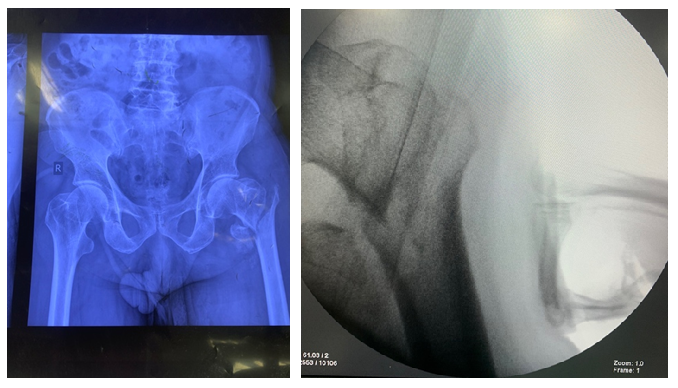

Fig. 1: Left IT femur #

Initially, closed reduction was attempted using internal rotation and longitudinal traction. In cases where closed reduction was not feasible, a mini-open approach was employed. This involved making a small longitudinal incision approximately 5 cm proximal to greater trochanter. Gluteal fascia was incised, and gluteus medius was split longitudinally to access tip of trochanter. The correct entry point for nail was determined using fluoroscopy, and a guide wire was advanced from trochanter to medulla (fig. 2).